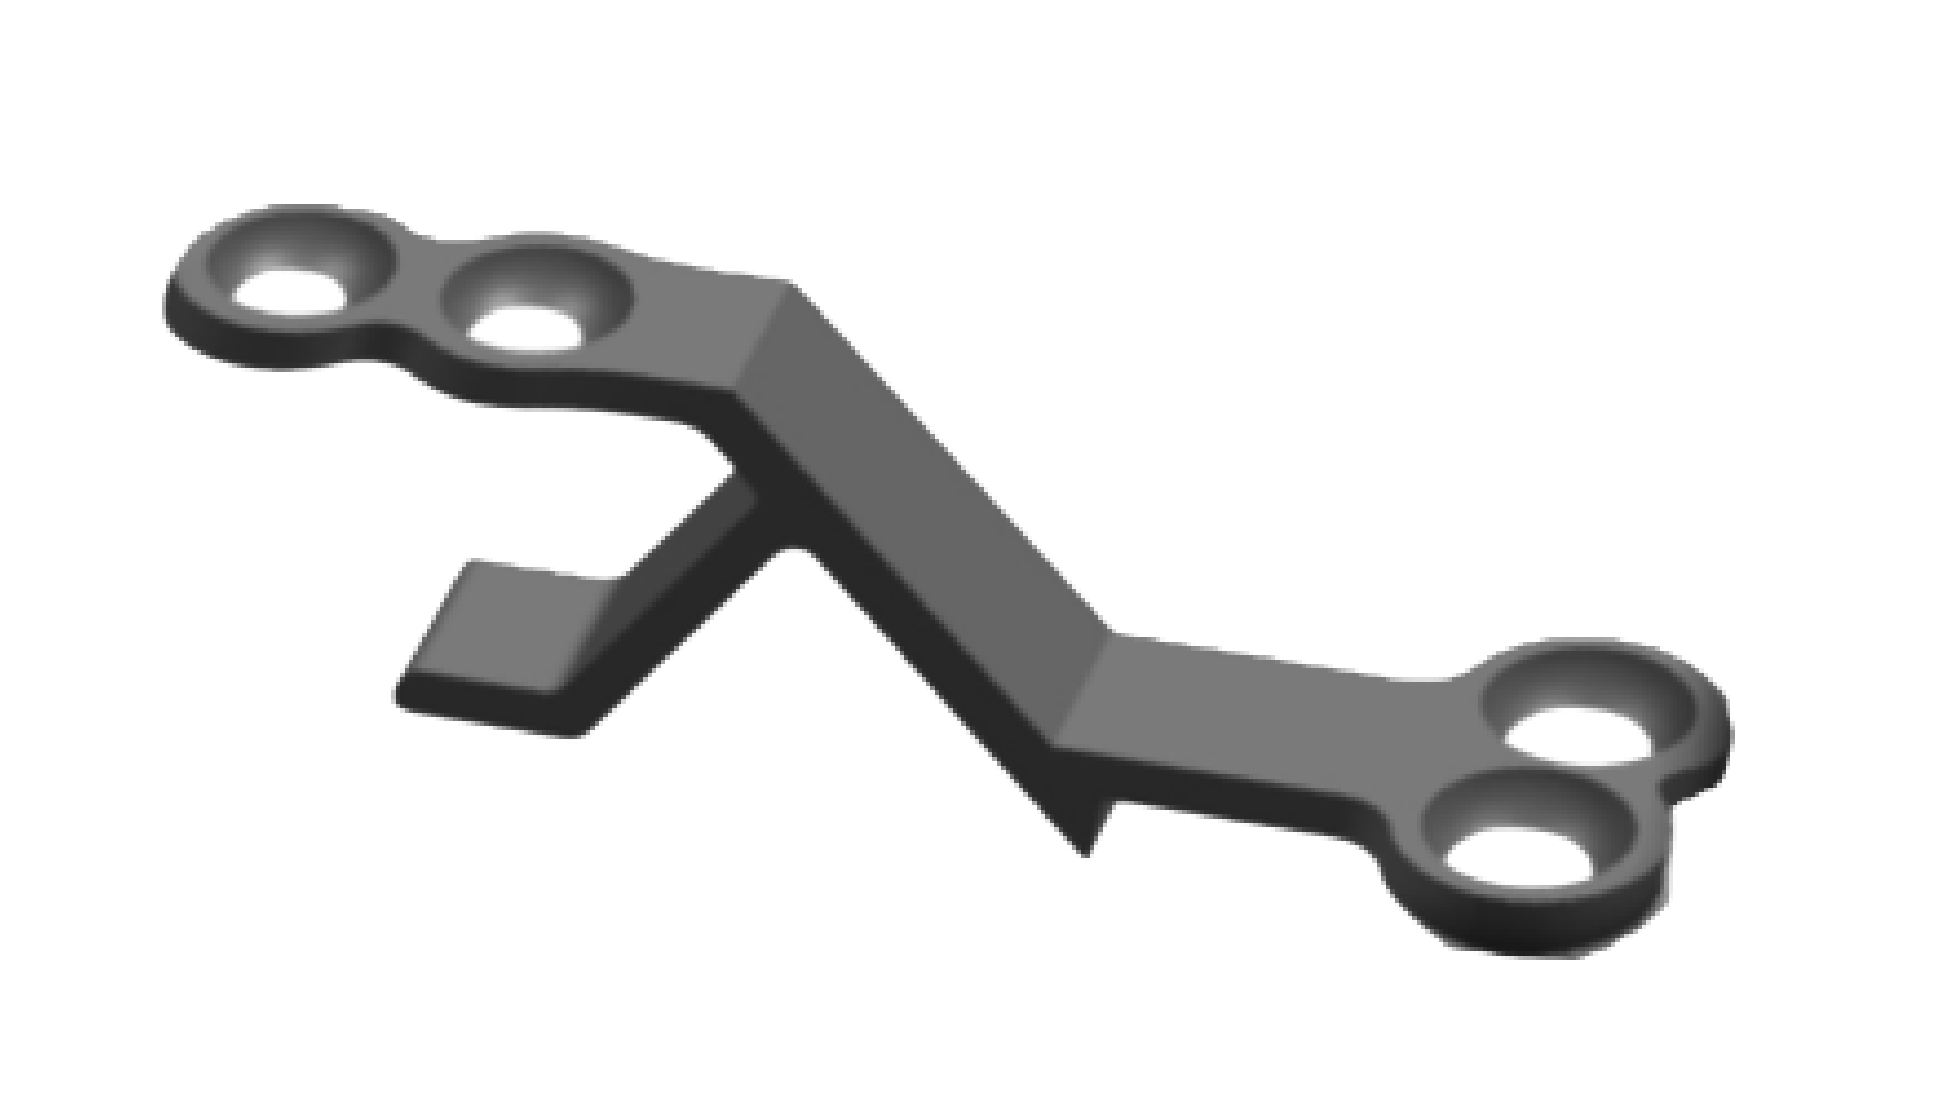

Spinal Lamina Fixation Plate System